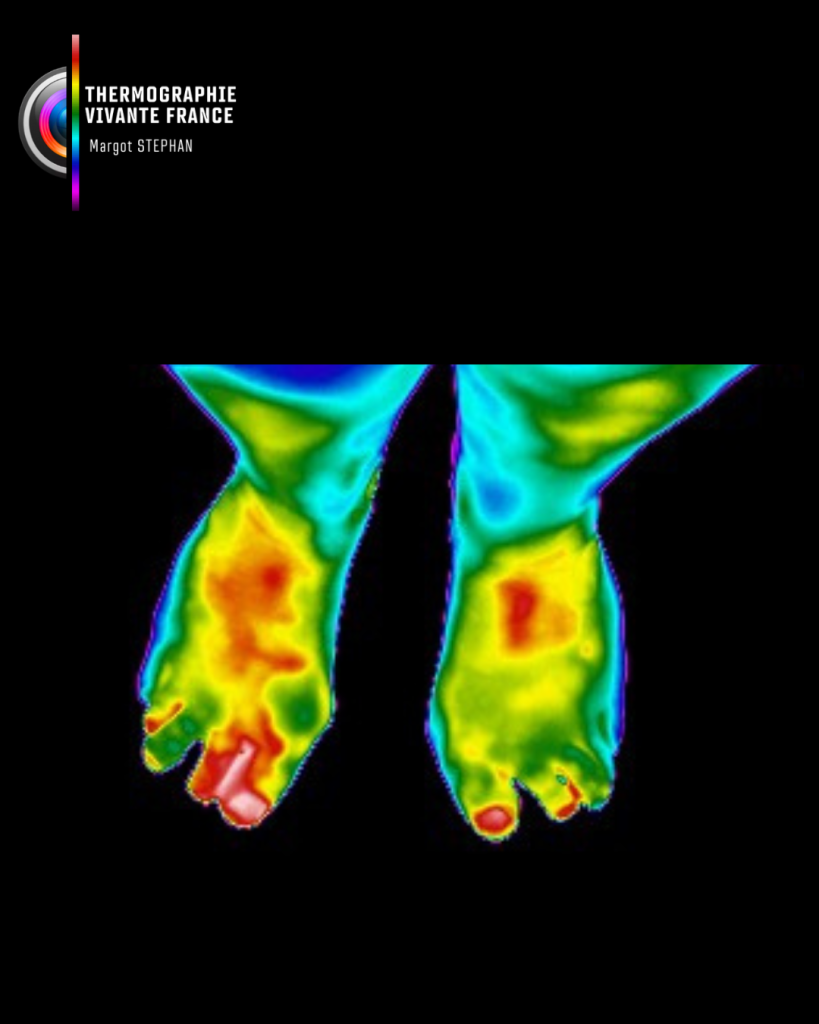

La thermographie vivante est une méthode d’imagerie fonctionnelle non invasive, sans contact, sans rayons, indolore, qui permet de visualiser la carte thermique du corps humain. Elle détecte les variations de température cutanée, révélatrices de phénomènes physiologiques internes : inflammation, surcharge fonctionnelle, tension musculaire, déséquilibres vasculaires, métaboliques ou neurologiques.

Elle révèle plutôt comment ces tissus fonctionnent en temps réel, en mesurant les émissions naturelles de chaleur générées par l’activité métabolique du corps.

La température cutanée que la caméra thermique capte n’est pas un simple reflet de la peau. Elle exprime les interactions profondes entre les systèmes vasculaire, neuromusculaire, inflammatoire et endocrinien.

Elle permet ainsi de détecter :

- Des zones de surchauffe (inflammation, surcharge fonctionnelle)

- Des zones de froid anormal (hypoactivité, trouble circulatoire, déconnexion neurovasculaire)

- Des asymétries thermiques révélant une compensation posturale ou une perturbation fonctionnelle

Un déséquilibre thermique au mollet ? Parfois lié à un trouble postural dentaire.

C’est cette lecture systémique, intelligente et comparative qui fait toute la richesse de la thermographie vivante.